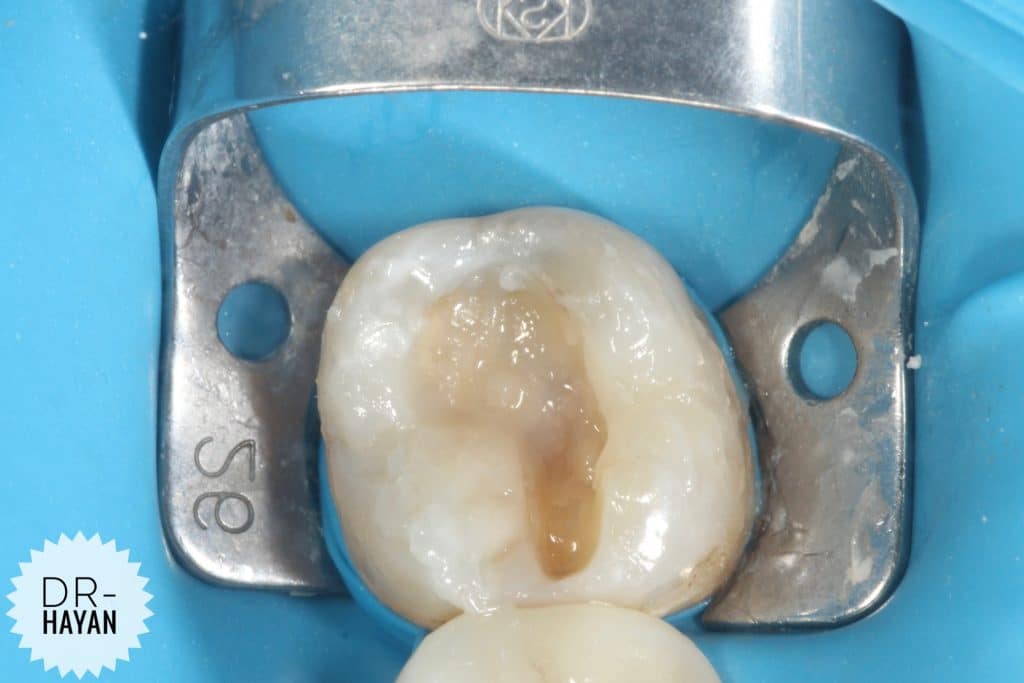

Finishing the floor And

Remove any sharp angle

After that

IDPC

Selective etch

- finishing the gingival seat by sharp excavator

- After etching dis infected the cavity by CHX

And dry it only